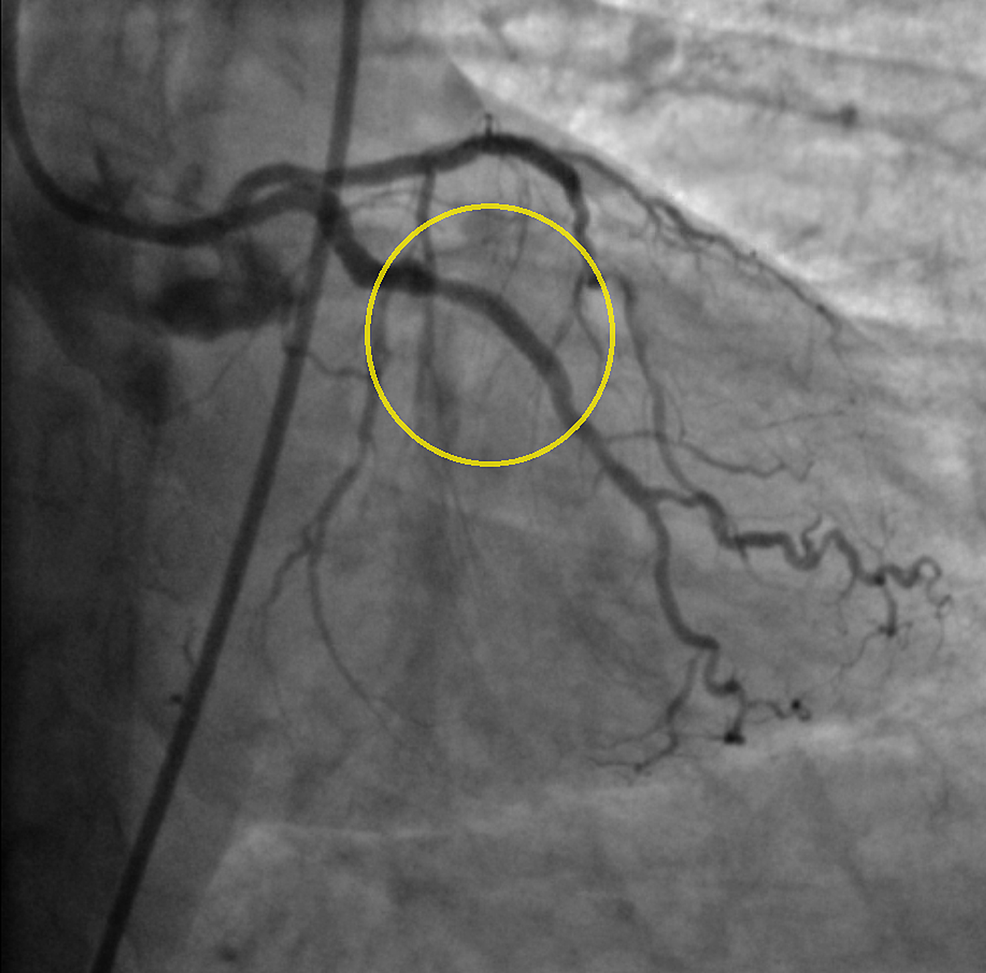

Figure 2 from Successful Percutaneous Balloon Angioplasty in a Patient Intracranial Balloon Angioplasty We aimed to compare efficacy and safety of acute carotid artery stenting to balloon angioplasty alone on treating the cervical lesion in tandem occlusions. In the present series, we evaluated the role and need of intracranial balloon angioplasty with dedicated maverick system in symptomatic. Balloon angioplasty alone is the first and simplest endovascular therapy used for the treatment of intracranial. Intracranial Balloon Angioplasty.

An example of a case with balloon angioplasty and intracranial stenting Intracranial Balloon Angioplasty We aimed to compare efficacy and safety of acute carotid artery stenting to balloon angioplasty alone on treating the cervical lesion in tandem occlusions. Design balloon angioplasty for symptomatic intracranial artery stenosis (basis) trial is a multicentre, prospective, randomised,. The first successful intracranial balloon angioplasty was reported in 1980, and multiple case series and retrospective studies. The balloon angioplasty for. Intracranial Balloon Angioplasty.